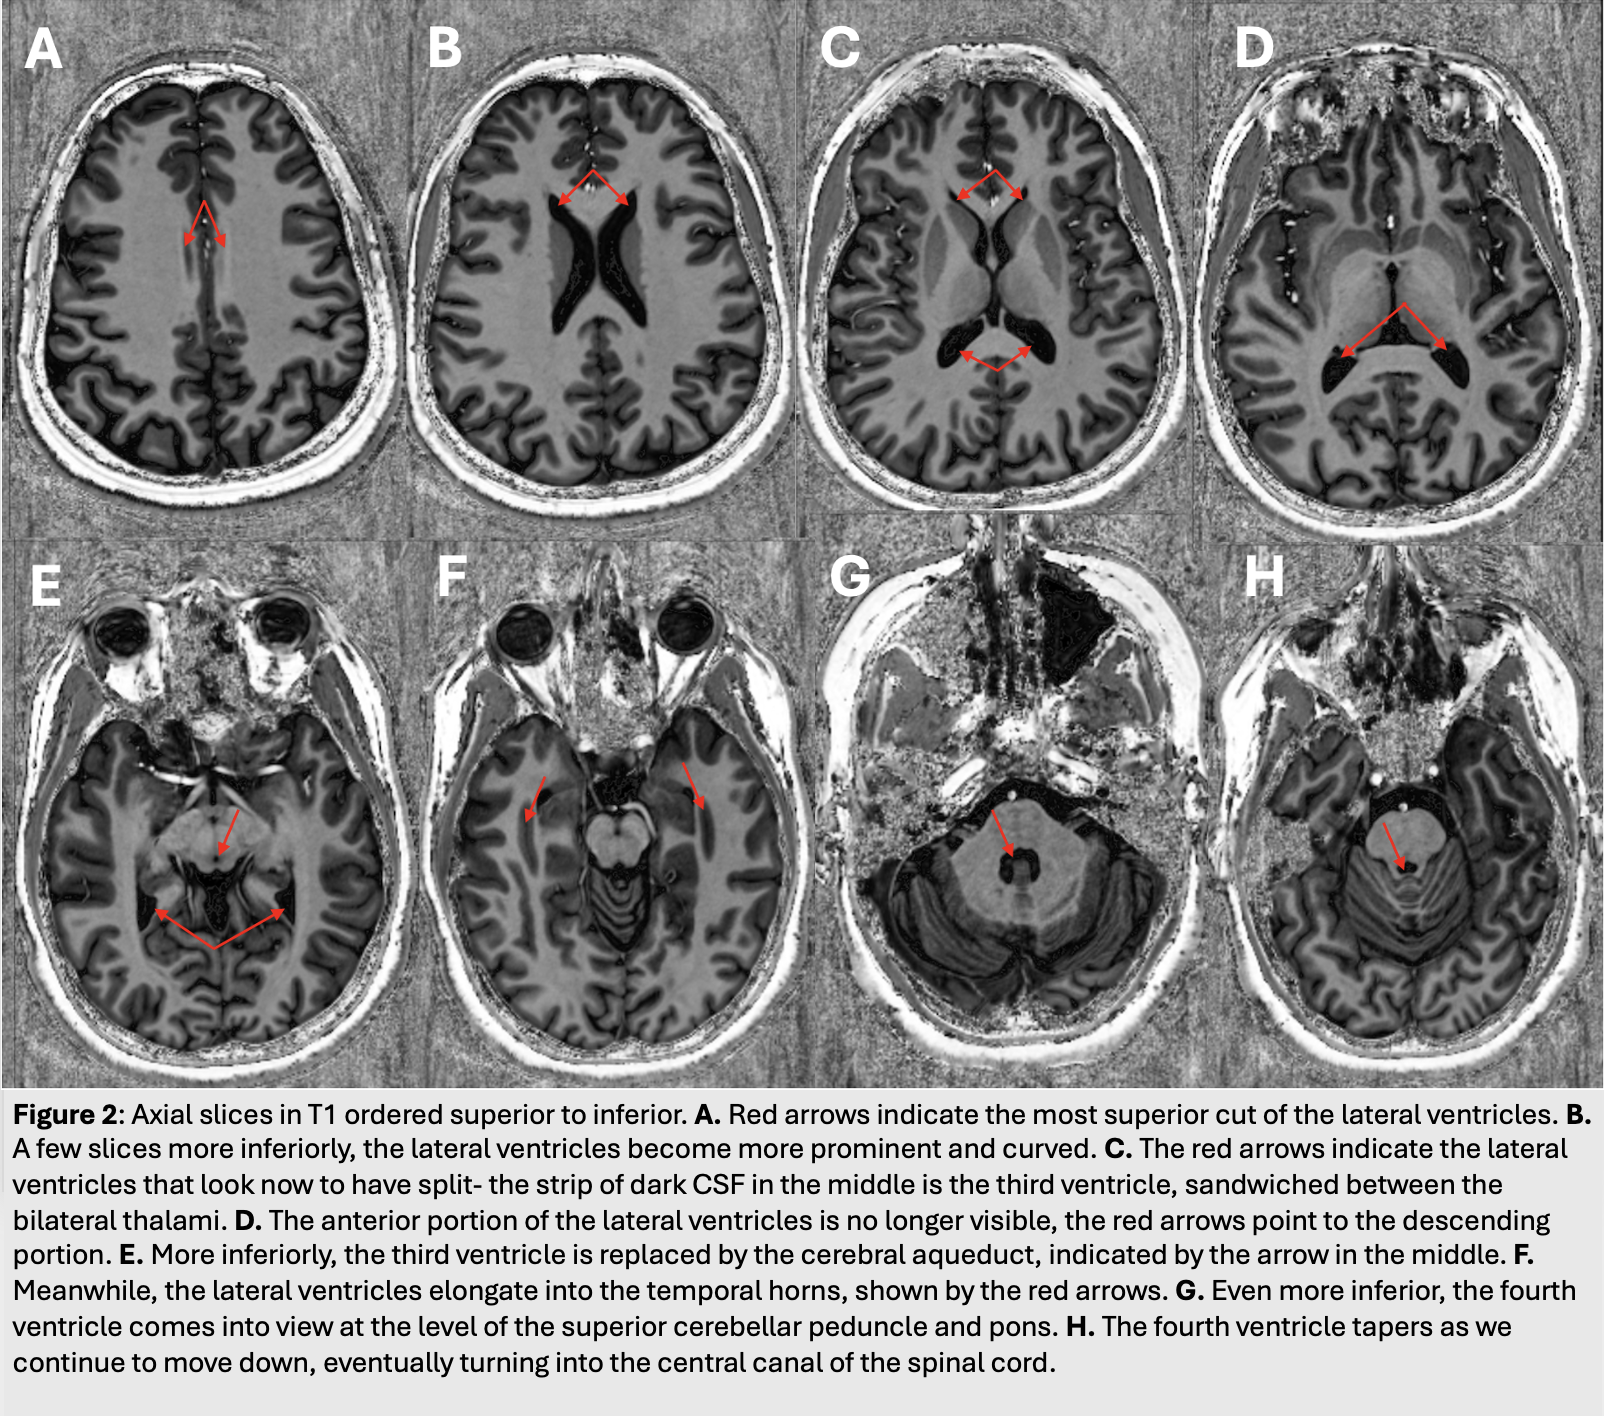

• Figure 2: Axial slices in T1 ordered superior to inferior. A) Red arrows indicate the most superior cut of the lateral ventricles. B) A few slices more inferiorly, the lateral ventricles become more prominent and curved. C) The red arrows indicate the lateral ventricles that look now to have split- the strip of dark CSF in the middle is the third ventricle, sandwiched between the bilateral thalami. D) The anterior portion of the lateral ventricles is no longer visible, the red arrows point to the descending portion. E) More inferiorly, the third ventricle is replaced by the cerebral aqueduct, indicated by the arrow in the middle. F) Meanwhile, the lateral ventricles elongate into the temporal horns, shown by the red arrows. G) Even more inferior, the fourth ventricle comes into view at the level of the superior cerebellar peduncle and pons. H) The fourth ventricle tapers as we continue to move down, eventually turning into the central canal of the spinal vord